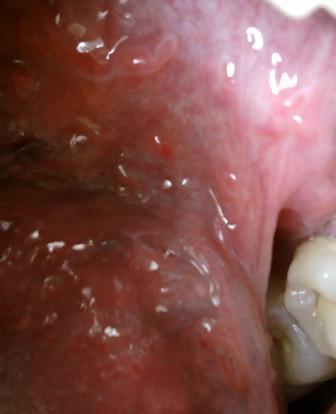

石家庄九州皮肤病医院 > 尖锐湿疣 > > > 抽烟饮酒会不会成为诱发尖锐湿疣的罪魁祸首尖锐湿疣性病现在的发病原因是比较多的,发病原因也是比较复杂的,其中抽那饮酒会导致人体免疫力低下,进而会诱发各种疾病,这一点希望大家应了解。

抽烟饮酒会不会成为诱发尖锐湿疣的罪魁祸首抽烟饮酒对于人体健康危害很大。因此维为了身体健康,应该养成一个良好的健康的生活方式。以免不慎感染病毒而患病。尖锐湿疣病毒是比较顽固的,一般传染途径会通过以下几种方式:直接接触传染,间接接触传染和母婴传染。传染途径如此广泛,因此在平时应该注意做好疾病的工作。